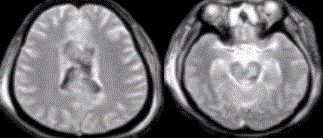

- [材料题] 患者,男性,27岁。车祸外伤后昏迷,X线平片与CT未见明确骨折及颅内血肿,MR表现如下图。

- 单项选择题1.正确的诊断是( )。

A、蛛网膜下隙出血

B、脑皮质挫裂伤

C、脑室出血

D、脑梗死

E、弥漫性轴索损伤

- 单项选择题2.有关该病的叙述不正确的是( )。

A、脑组织在创伤造成的减速运动中,因皮、髓质质量不一致产生剪力而致轴索的撕裂

B、影像学表现与临床预后不一致

C、CT检查可明确诊断

D、病变主要见于灰、白质交界区,脑干,胼胝体等部位

E、MR T2WI可清晰显示病变,与T2WI相比,SWI更敏感

- 单项选择题3.弥漫性轴索损伤的影像学表现,表述不正确的是( )。

A、磁敏感加权像较GRE能发现更多的病灶

B、MRI表现为多灶性T2WI高信号,慢性期可呈低信号

C、GRE T2WI显示微小出血灶敏感,由于磁敏感效应,病变呈多发低信号

D、DWI显示病变呈高信号,ADC图呈低信号,DTI可显示白质损伤的程度

E、MRS显示NAA下降,提示神经元损伤与预后相关,Cho无变化